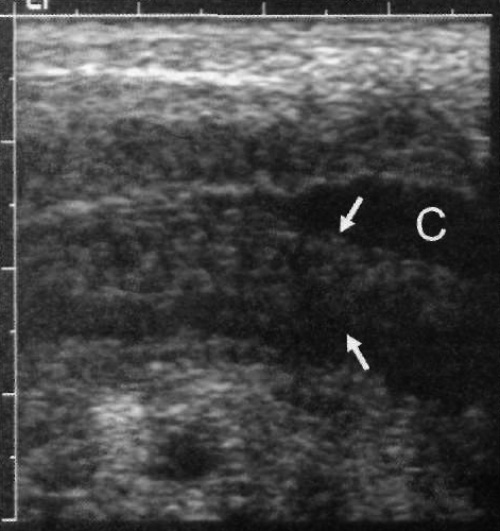

К дополнительным ультразвуковым критериям аппендицита можно отнести усиление кровотока в толще стенки неперфоративного червеобразного отростка (при проведении цветовой допплерографии), а также визуализацию периаппендикулярного жира (фото 4). Могут определяться периаппендикулярные воспалительные изменения, газ или жидкость (фото 5). В некоторых случаях визуализируются эхогенные фекальные конкременты, которые дают акустическую тень. Также может наблюдаться большое количество увеличенных брыжеечных лимфоузлов (фото 6).

Фото 5. Аппендицит. Ультразвуковое изображение правого нижнего квадранта живота в продольной проекции: стрелками обозначено монстрирующее увеличение червеобразного отростка, в периаппендикулярной клетчатке наблюдается скопление жидкости (С)